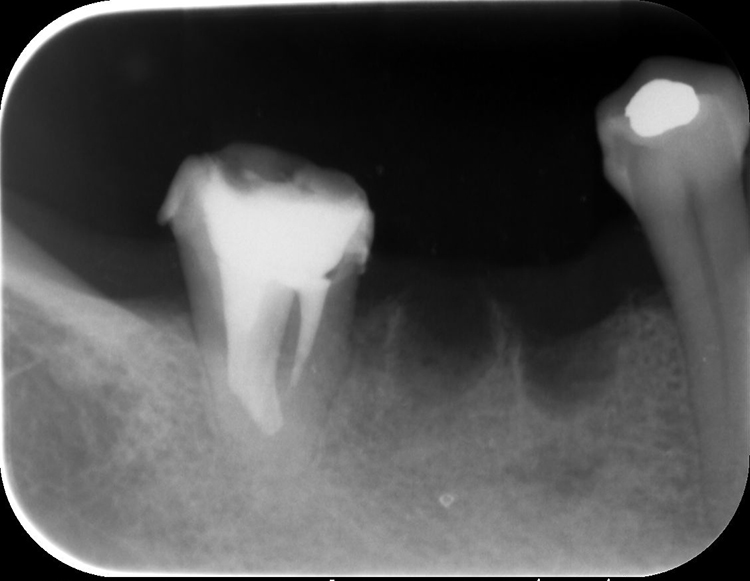

保険で治療していた左上5番の金属を外し虫歯を取りながら根管治療を行います。次回来院時にファイバーコア(土台)を築造して仮歯で組織を安定させます。患者さんが自覚してなかった根尖病巣が右上2番にあり、歯ぐきに膿の袋(フィステル)が露出している状態でした。ラバーダムと隔壁で治療中の感染を防止して、マイクロスコープによる拡大視野のもと根管を丁寧に消毒したあと、ファイバーコア(土台)を築造し仮歯で整えました。

右下6番は保存不可能な状態で根尖病巣があったため抜歯となりました。経過観察しながら組織の回復後にインプラントの予定です。こうした治療の間も食事が不便になせないように左側を噛めるように残しています。

保存可能な右下7番(大臼歯)の金属の詰め物を取り外しマイクロスコープによる拡大視野のもと根管を丁寧に消毒し、ファイバーコア(土台)を築造し仮歯で整えました。